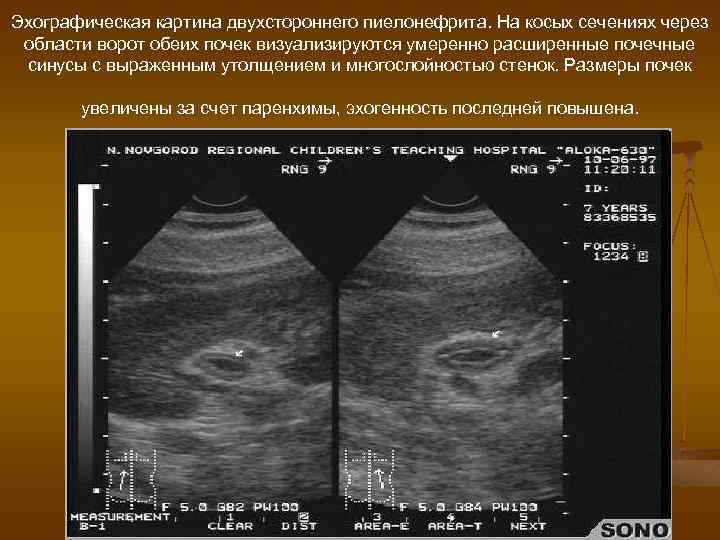

Эхографическая картина двухстороннего пиелонефрита. На косых сечениях через области ворот обеих почек визуализируются умеренно расширенные почечные синусы с выраженным утолщением и многослойностью стенок. Размеры почек увеличены за счет паренхимы, эхогенность последней повышена.